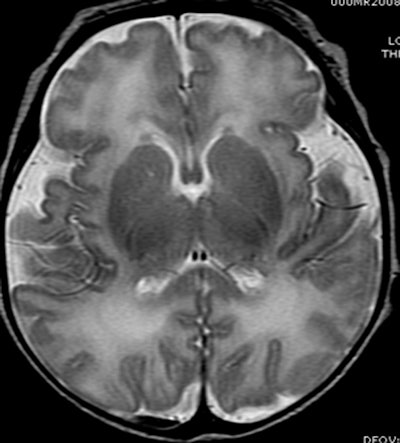

While some white-matter damage is readily apparent on MRI, the current study uses MR spectroscopy to investigate the differences on a microscopic level.

The researchers compared the concentrations of certain chemicals associated with mature white matter and gray matter in 51 full-term and 30 preterm infants. Subjects had normal structural MRI findings, but MR spectroscopy showed significant differences in the biochemical maturation of white matter between term and preterm infants.

The findings suggest there is a disruption in the timing and synchronization of white- and gray-matter maturation. In the premature infants, white-matter development had an early start and was out of sync with gray-matter development, Blüml noted.